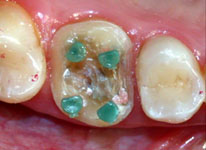

Fig. 9

O kit do Sistema Paramax é fornecido com as brocas tipo trépano (Paramax Drillis 0,7mm OrtoPins) , pinos plásticos para moldagem e confecção do padrão e pinos de alumínio para a provisória.

Fig. 10

Pinos de nylon posicionados nos orifícios para reproduzir a localização, diâmetro e profundidade dos mesmos.

Com a broca tipo trépano (Paramax Drillis 0,7mm OrtoPins da Coltène Whaledent, USA), a qual apresenta limitador de penetração, confeccionou-se quatro perfurações com 2 milímetros de profundidade, localizadas nas regiões correspondentes às bases das cúspides (Fig. 6 e 9). Estes orifícios e a área de atrito friccional conseguida com o bisel chanfrado periférico de forma côncava, evitaram a confecção de núcleo e o preparo para coroa total, preservando a vitalidade pulpar do dente e os limites cervicais localizados supragengivalmente.

Para conseguir o paralelismo entre os orifícios, um fio ortodôntico foi inserido na primeira perfuração, o que auxiliava no posicionamento paralelo da broca no momento da realização do segundo orifício e, assim sucessivamente, até a última perfuração (Fig. 7).